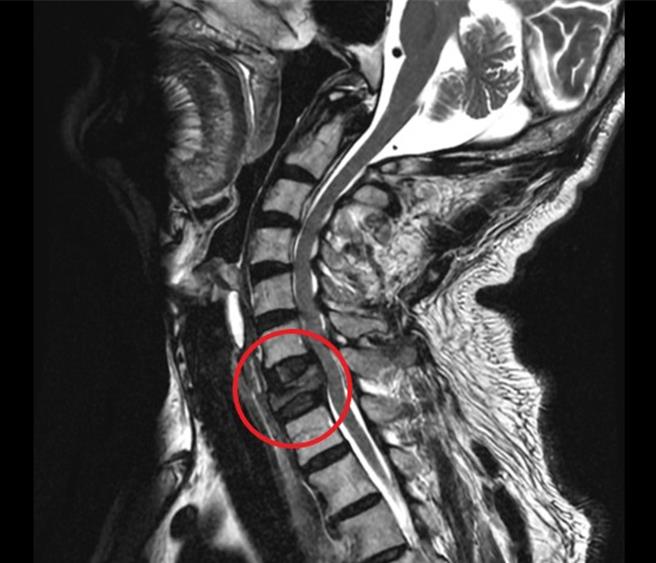

男子從2個月前開始出現頸部和雙肩酸痛的症狀,還感到放射痛及雙上肢麻木,尤其左上臂內側出現劇烈疼痛,雖服用止痛藥,症狀卻毫無改善。經活力得中山脊椎外科醫院使用頸椎X光和MRI(核磁共振)檢查顯示,患者頸椎第七節有病理性爆裂骨折和椎管內惡性腫瘤,且懷疑癌細胞已轉移至大腸。

在楊淑喬建議下,男子接受手術治療,使用椎體前側置換裝置,亦即新式撐開型支架,維持頸椎穩定度。術後恢復良好,不過大腸癌部分仍相當頭痛,目前仍在接受治療。

楊淑喬指出,患者曾赴醫學中心等多家醫療院所接受X光檢查及治療,但X光檢查無法顯示頸椎第七節的異常,沒能揪出真正病因,才會拖延到癌細胞擴散,所幸及早發現腫瘤,對大腸癌的治療也有即時性。